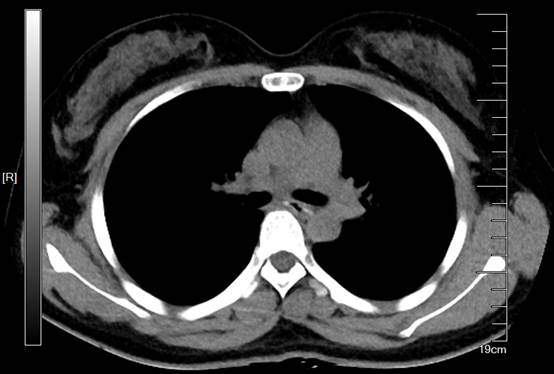

术后小程复查了胸部CT,食管中段没有再看到异物,周围组织也没有异常,在中心ICU观察一天后顺利出院。

图4 术后CT